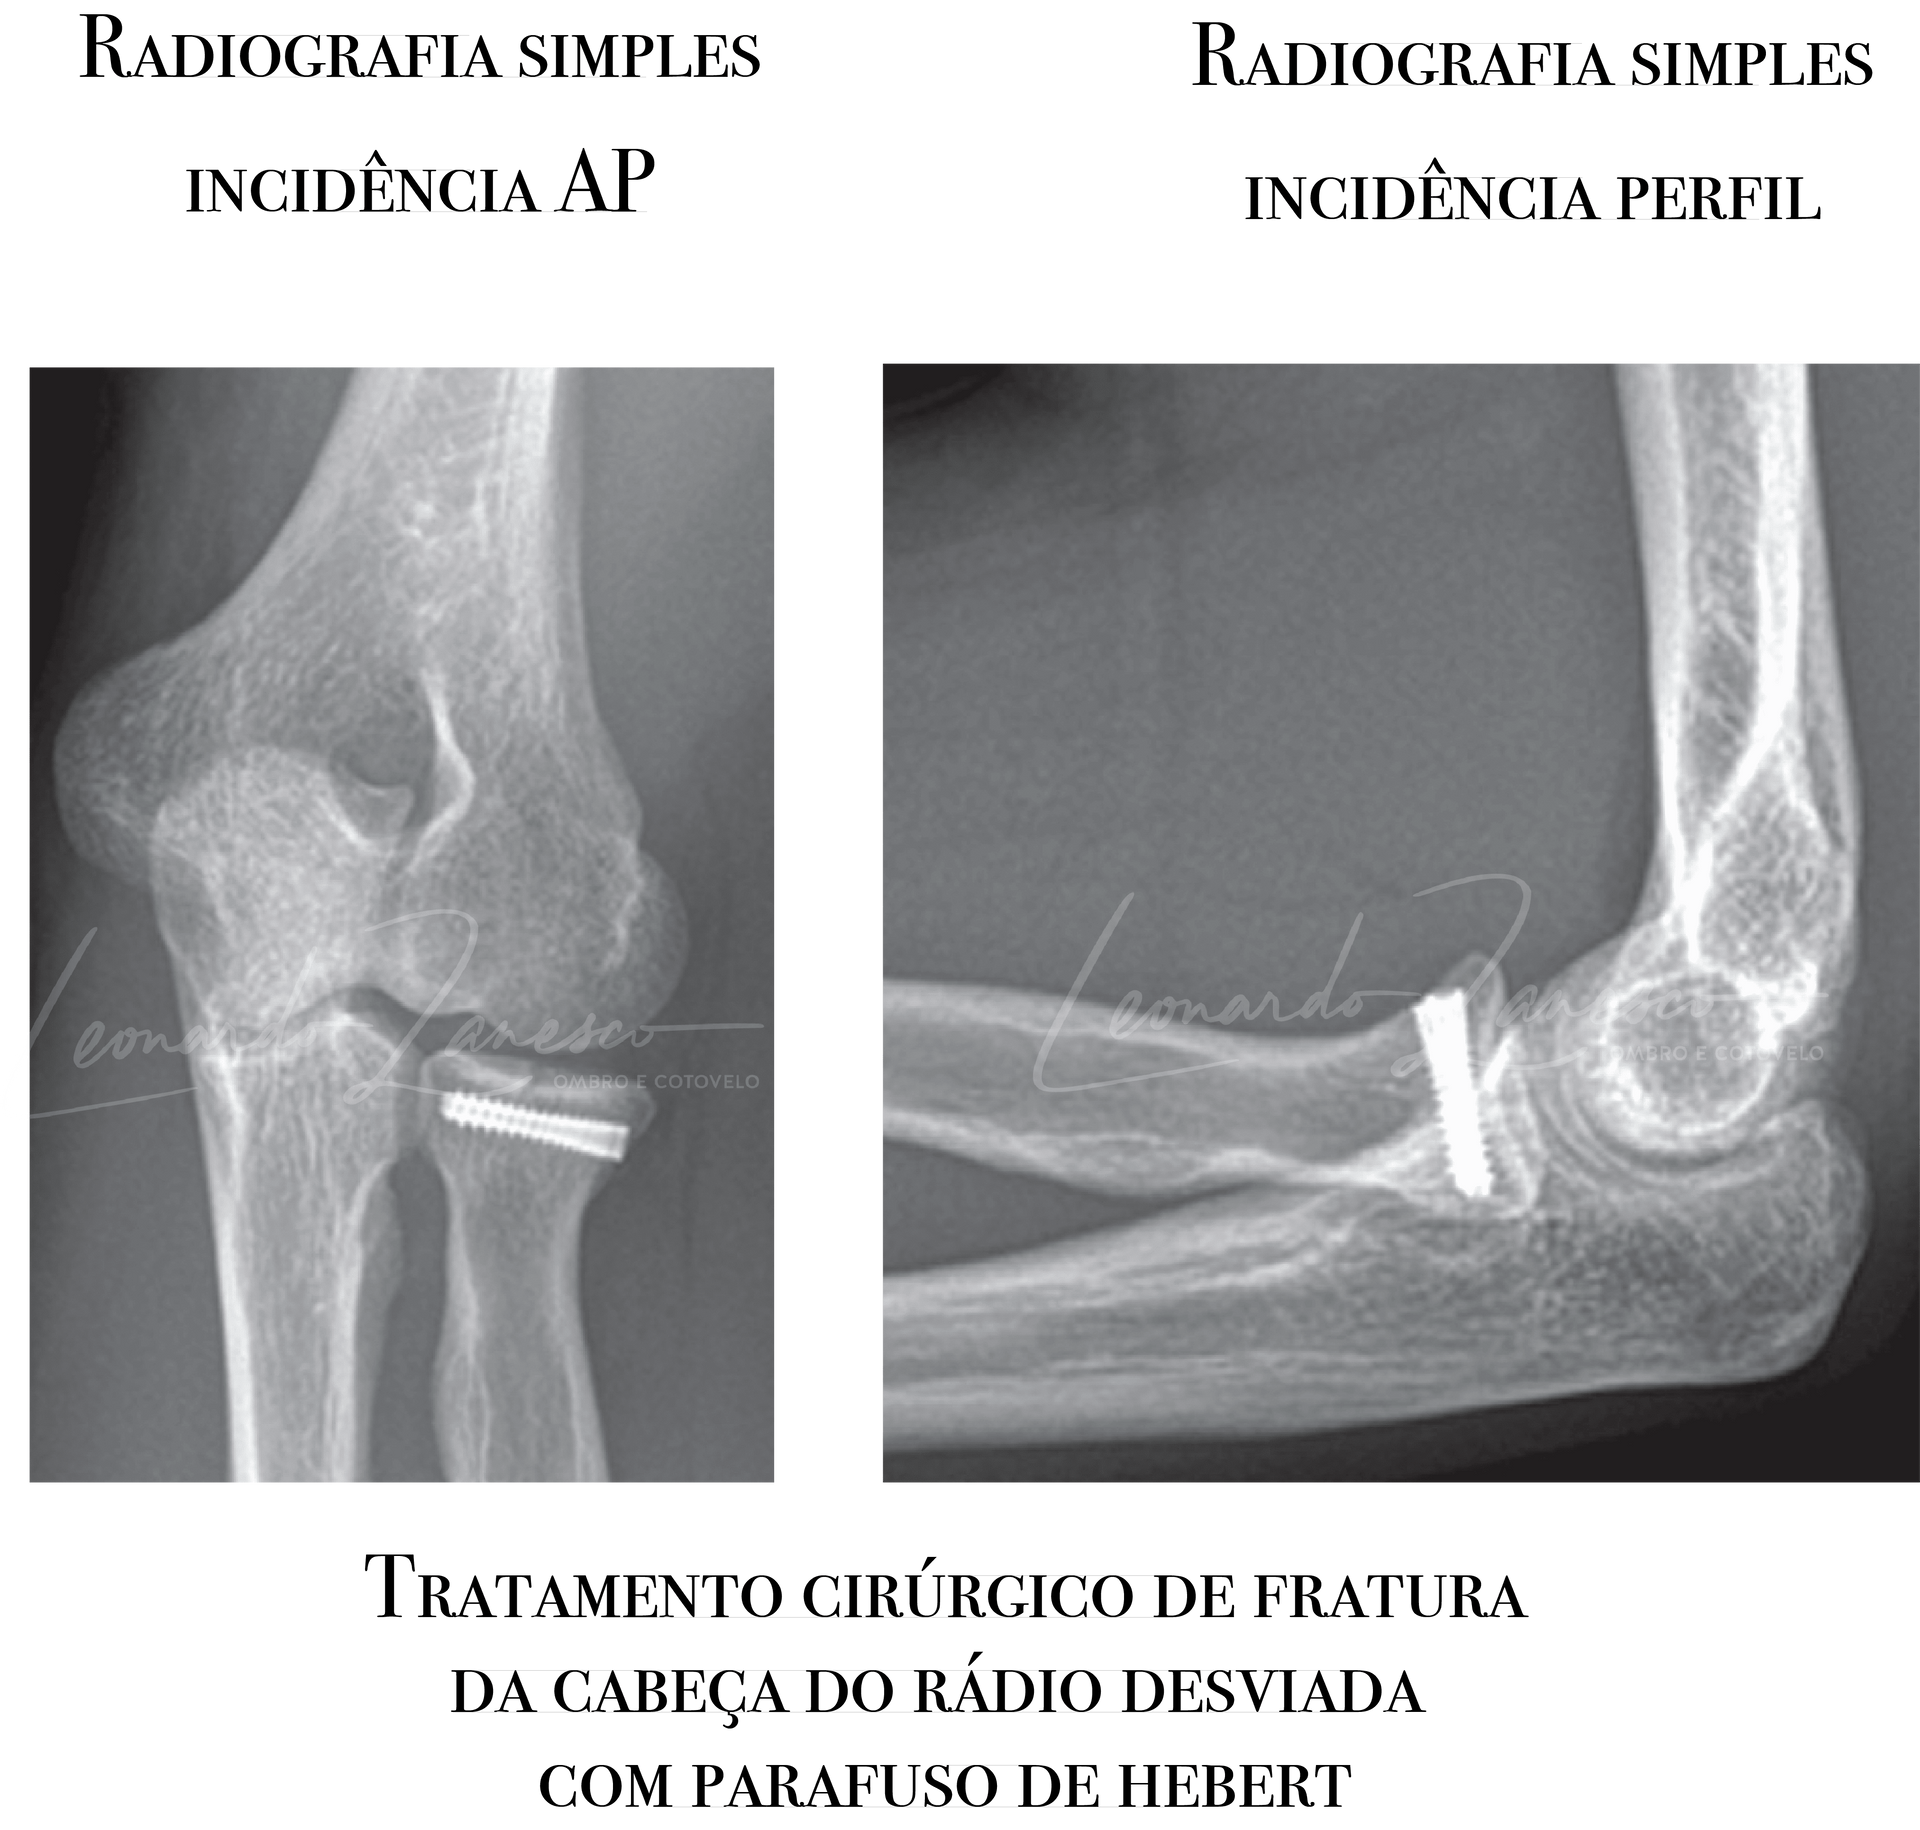

- Reconstrução com placa e parafuso (ORIF): Indicada nas fraturas desviadas e reconstruíveis, especialmente em pacientes jovens, tipicamente quando há três ou menos fragmentos e boa cartilagem. Sinais clássicos usados como guia são desvio >2 mm e acometimento >30% da superfície articular (Mason II), embora a superioridade de operar todos esses casos não esteja definitivamente provada. Em fraturas com >3 fragmentos, os riscos de não união, osteonecrose, falha de fixação e rigidez aumentam; parafusos “countersunk” tendem a gerar menos rigidez do que placas.

Radiografias em AP e perfil costumam fazer o diagnóstico quando há desvio; nas fraturas sem desvio, os sinais do coxim gorduroso (anterior e posterior) podem ser a única pista inicial. A incidência radiocapitelar ajuda a perfilar a cabeça do rádio. Para definir com precisão o número de fragmentos, localização e grau de desvio — e para pesquisar lesões associadas (coronoide, capitelo, fragmentos osteocondrais) — a tomografia é o método preferencial. Ressonância raramente é necessária na fase aguda.